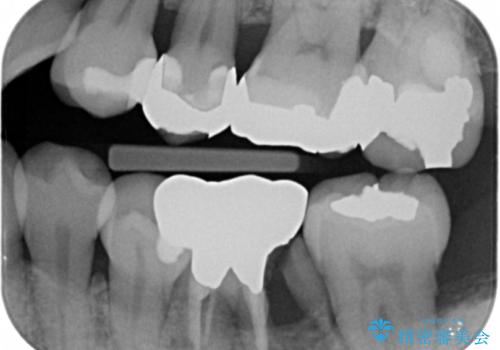

- 左下奥歯の歯ぐきの違和感で来院。

昔神経の治療をした歯が割れてしまっていました。

やむなく抜歯になりましたが、その部分にインプラントを始め希望されましたが、炎症により、骨がなく、かつ歯並びの関係で入れても歯ブラシができずにインプラントも長くもたなそうという診断になりました。

インプラントではなくブリッジにするためには、奥歯の並びを矯正しておいた方がいい状態でした。

抜歯後に部分的にワイヤー矯正を半年ほど行ってから、ブリッジを入れる治療を行いました。